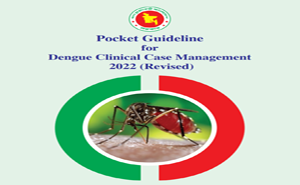

Download Dengue Pocket Guideline